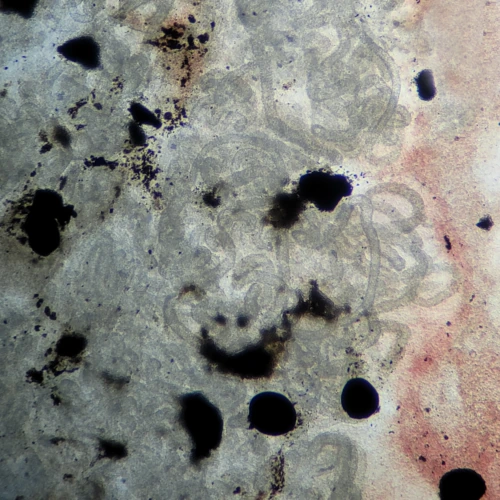

Туловищная почка располагается вдоль позвоночника под плавательным пузырём и содержит почечные канальцы — основные функциональные структуры. Через неё проходит значительный объём крови, поэтому нарушения микроциркуляции быстро приводят к выраженным изменениям.

Характерные признаки:

- гиперемия

- деструкция канальцев

- некроз ткани

При хроническом течении ГПЗ рыбы могут доживать до подобных стадий. Гибель при пересадке или стрессе в таких случаях является следствием уже развившихся изменений, а не их причиной.